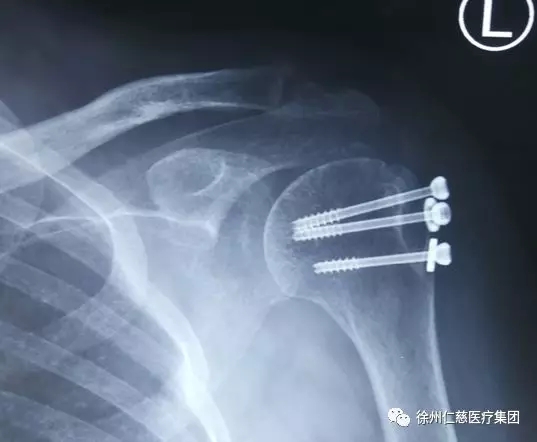

受伤后,邢大姐立刻前往我市一家三甲医院治疗,经诊断,其左肩关节脱位、左肱骨大结节撕脱骨折、肋骨骨折。

经肌电图检查显示,邢大姐的左侧腋神经已完全受损,这意味着,该处神经已无法自行恢复。

“大姐,您别急,抬胳膊、肩外展这些功能,我们一定想办法帮您恢复!”接诊的手外科三病区陈步国主任一边耐心地安抚病人,一遍仔细查看伤情。陈步国主任发现,邢大姐左肩仅能外展约30°,三角肌萎缩,三角肌皮肤区域感觉减退……在腋神经完全受损的情况下,要想恢复功能,只有一个办法:神经移位!

陈步国主任手术小组先在患者腋下做一长约15cm“S”形切口,探查见患者四边孔周围疤痕组织增生严重,腋神经与周围疤痕组织粘连明显,陈主任将患者周围疤痕粘连组织松解后,术中用肌电图刺激神经,提示左侧腋神经完全损害,左侧肌皮神经、桡神经三头肌肌支呈现正常生理表现。如果不重建修复,恢复腋神经功能,那么患者肩关节部分功能将会丧失。